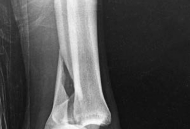

Partial articular fractures, classified under the AO/OTA alphanumeric system as Type B fractures, represent a complex subset of orthopedic injuries where a portion of the articular surface is disrupted while the remainder of the joint remains in continuity with the metaphyseal and diaphyseal regions. The fundamental objective in the surgical management of these fractures is the restoration of articular congruity and the provision of absolute stability to permit early, active mobilization. Unlike extra-articular or diaphyseal fractures where relative stability and secondary bone healing via callus formation are acceptable, partial articular fractures demand anatomic reduction and primary bone healing to mitigate the risk of post-traumatic osteoarthritis.

The epidemiology of partial articular fractures exhibits a classic bimodal distribution. High-energy trauma, such as motor vehicle collisions and falls from significant heights, predominantly accounts for these injuries in the younger, active demographic. In this cohort, fractures are frequently characterized by severe soft tissue compromise, marked displacement, and significant comminution (e.g., split-depression tibial plateau fractures or high-energy pilon variants). Conversely, low-energy mechanisms, typically ground-level falls, are responsible for partial articular fractures in the elderly population. This demographic presents unique challenges, including osteopenia or osteoporosis, which compromises implant purchase and increases the propensity for articular impaction and secondary subsidence.

The surgical execution for partial articular fractures follows a rigorous, algorithmic sequence: Exposure, Joint Visualization, Reduction, Provisional Fixation, and Definitive Plating. We will utilize the lateral tibial plateau fracture (AO/OTA 41-B) as the archetypal model to describe these steps.

Partial articular fractures typically present as a split (Type B1), depression (Type B2), or split-depression (Type B3).

1. Split Fractures: The peripheral fragment is hinged open like a book. Pointed reduction forceps (Weber clamps) are applied to the metaphyseal flare to compress the fragment back to the intact medial plateau.

2. Depression Fractures: A cortical window is created in the metaphysis distal to the fracture. A bone tamp is introduced through the window, and the depressed articular segment is carefully elevated under direct vision and fluoroscopic guidance.